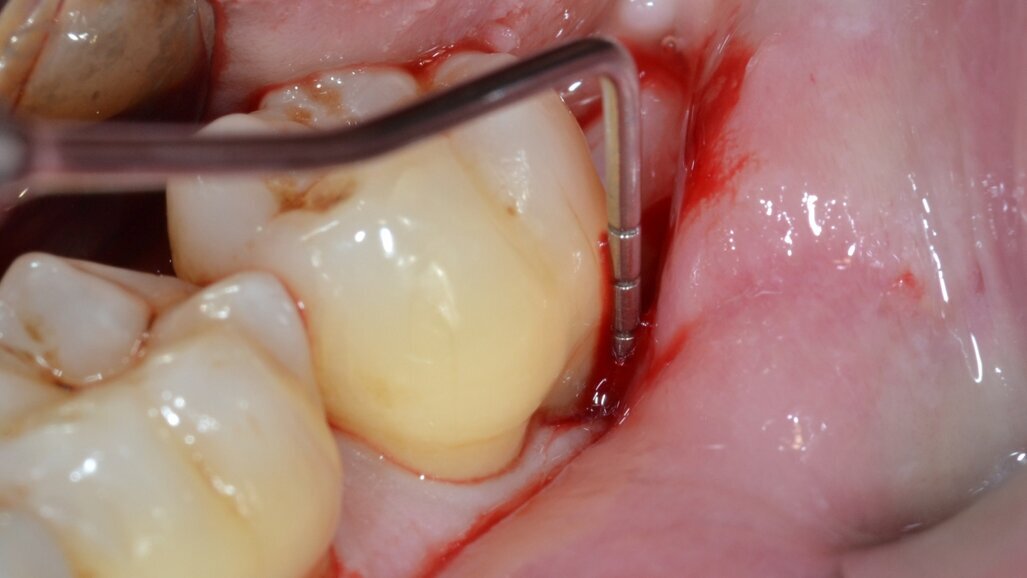

Dopo analgesia locale ottenuta per infiltrazione di Articaina cloridrato 40 mg con epinefrina 1:100.000 viene effettuata l’incisione di accesso secondo la tecnica denominata “Crestal Incision”4 per elevare un lembo a spessore totale che espone l’area interessata dal difetto (Fig. 5). Il debridement e la decontaminazione della superficie radicolare vengono effettuati per mezzo di inserti ultrasonici dedicati (Figg. 6, 7); al completamento di questo tempo chirurgico il difetto è innestato con biomateriale eterologo protetto da una membrana di tipo riassorbibile in pericardio di origine animale che viene fissata sulla cresta ossea mediante pins in titanio allo scopo di stabilizzare il coagulo e guidare la rigenerazione tissutale all’ interno del difetto. La ferita chirurgica è suturata con un filo riassorbibile 6/0 in PGA (Figg. 8-12).

Fig. 6 - Debridement del difetto intraosseo e decontaminazione della superficie radicolare mediante ultrasuoni (aspetto buccale).

Fig. 7 - Debridement del difetto intraosseo e decontaminazione della superficie radicolare mediante ultrasuoni (aspetto distale).